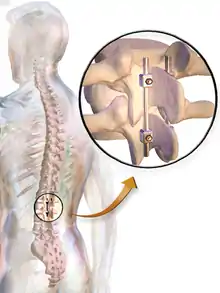

There are many types of spinal fusion techniques. Each technique varies depending on the level of the spine and the location of the compressed spinal cord/nerves.[4] After the spine is decompressed, bone graft or artificial bone substitute is packed between the vertebrae to help them heal together.[2] In general, fusions are done either on the anterior (stomach), posterior (back), or both sides of the spine.[4] Today, most fusions are supplemented with hardware (screws, plates, rods) because they have been shown to have higher union rates than non-instrumented fusions.[4] Minimally invasive techniques are also becoming more popular.[13] These techniques use advanced image guidance systems to insert rods/screws into the spine through smaller incisions, allowing for less muscle damage, blood loss, infections, pain, and length of stay in the hospital.[13] The following list gives examples of common types of fusion techniques performed at each level of the spine:

- Posterolateral fusion is a bone graft between the transverse processes in the back of the spine. These vertebrae are then fixed in place with screws or wire through the pedicles of each vertebra, attaching to a metal rod on each side of the vertebrae.

- Interbody Fusion is a graft where the entire intervertebral disc between vertebrae is removed and a bone graft is placed in the space between the vertebra. A plastic or titanium device may be placed between the vertebra to maintain spine alignment and disc height. The types of interbody fusion are:

- Anterior lumbar interbody fusion (ALIF) – the disc is accessed from an anterior abdominal incision

- Posterior lumbar interbody fusion (PLIF) – the disc is accessed from a posterior incision

- Transforaminal lumbar interbody fusion (TLIF) – the disc is accessed from a posterior incision on one side of the spine

- Transpsoas interbody fusion (DLIF or XLIF) – the disc is accessed from an incision through the psoas muscle on one side of the spine

- Oblique lateral lumbar interbody fusion (OLLIF) – the disc is accessed from an incision through the psoas muscle obliquely